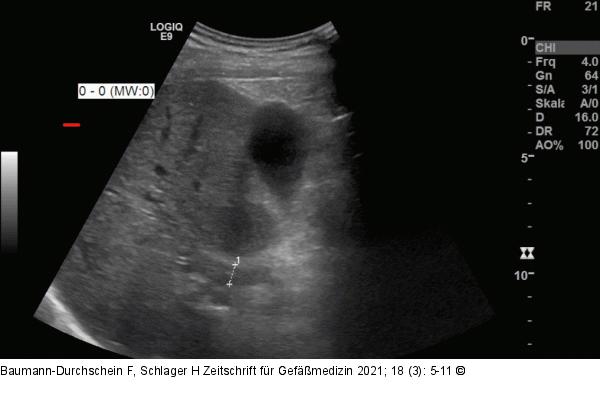

Abbildung 1: Pfortaderthrombose Abdomen-Sonographie bei chronischer Pfortaderthrombose in einer nicht zirrhotischen Leber. Das Lumen der V. portae ist durch thrombotisches Material verlegt (s. Markierung) |

Abdomen-Sonographie bei chronischer Pfortaderthrombose in einer nicht zirrhotischen Leber. Das Lumen der V. portae ist durch thrombotisches Material verlegt (s. Markierung) |